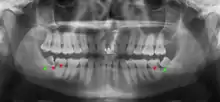

Wisdom teeth likely become impacted because of a mismatch between the size of the teeth and the size of the jaw. Impacted wisdom teeth are classified by their direction of impaction, their depth compared to the biting surface of adjacent teeth and the amount of the tooth's crown that extends through gum tissue or bone. Impacted wisdom teeth can also be classified by the presence or absence of symptoms and disease. Screening for the presence of wisdom teeth often begins in late adolescence when a partially developed tooth may become impacted. Screening commonly includes a clinical examination as well as x-rays such as panoramic radiographs.

Impacted wisdom teeth are classified by the direction and depth of impaction, the amount of available space for tooth eruption, and the amount of soft tissue or bone (or both) that covers them. The classification structure helps clinicians estimate the risks for impaction, infections and complications associated with wisdom teeth removal.[6] Wisdom teeth are also classified by the presence (or absence) of symptoms and disease.[7]

One review found that 11% of wisdom teeth will have evidence of disease and are symptomatic, 0.6% will be symptomatic but have no disease, 51% will be asymptomatic but have disease present and 37% will be asymptomatic and have no disease.[7] Impacted wisdom teeth are often described by the direction of their impaction (forward tilting, or mesioangular being the most common), the depth of impaction and the age of the patient as well as other factors such as pre-existing infection or the presence of pathology (cysts, tumors or other disease).[5]: 143–144 Each of these factors is used to predict the difficulty (and rate of complications) when removing an impacted tooth, with age being the most reliable predictor[8] rather than the orientation of the impaction.[9]